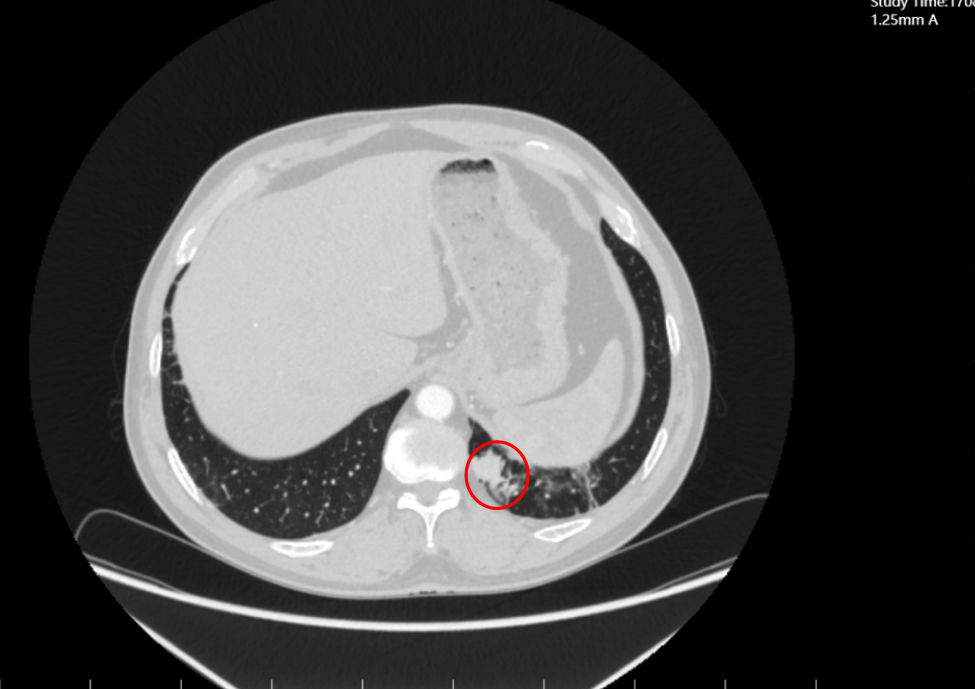

治疗期间依托科室影像诊断技术(高分辨率CT)、实验室检测技术(肿瘤标志物动态监测),建立“周度评估+月度复查”的技术监测体系:

2023年11月(联合治疗5周期),CT显示肺部原病灶大部分退缩为磨玻璃影,技术层面验证“肿瘤活性显著降低”;